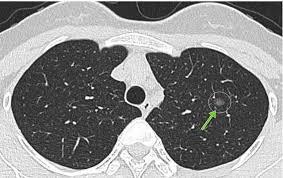

“双肺可见多发小结节影,大小约 2–5mm,边界清晰 / 模糊不等。”

定义:肺小结节是指肺内直径小于3厘米的类圆形密度影;

当结节直径 ≤6mm 时,称为“小结节”或“微结节”;

CT 扫描中看到了多个微小阴影,但它们的性质暂时未定。

“多数 3–5mm 小结节都是良性的炎症残影。真正需要关注的,是那些‘单侧、毛刺状、在短期复查中长大的’结节。”